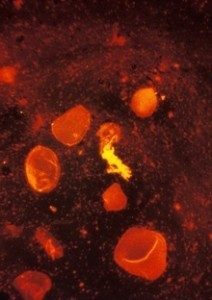

A test for TB, a sputum smear stained using fluorescent acid fast stain © CDC/R W Smithwick

Smear microscopy of sputum is often the first test to be used in countries with a high rate of TB infection. Sputum is a thick fluid that is produced in the lungs and the airways leading to the lungs. A sample of sputum is usually collected by the person coughing. Several samples of sputum will normally be collected.5 In 2012 it was suggested that two specimens can be collected on the same day without any loss of accuracy.6 7

To do the test a very thin layer of the sample is placed on a glass slide, and this is called a smear. A series of special stains are then applied to the sample, and the stained slide is examined under a microscope for signs of the TB bacteria.8

Sputum smear microscopy is inexpensive and simple, and people can be trained to do it relatively quickly and easily. In addition the results are available within hours. The sensitivity though is only about 50-60%.9 In countries with a high prevalence of both pulmonary TB and HIV infection, the detection rate can be even lower, as many people with HIV and TB co-infection have very low levels of TB bacteria in their sputum, and are therefore recorded as sputum negative.